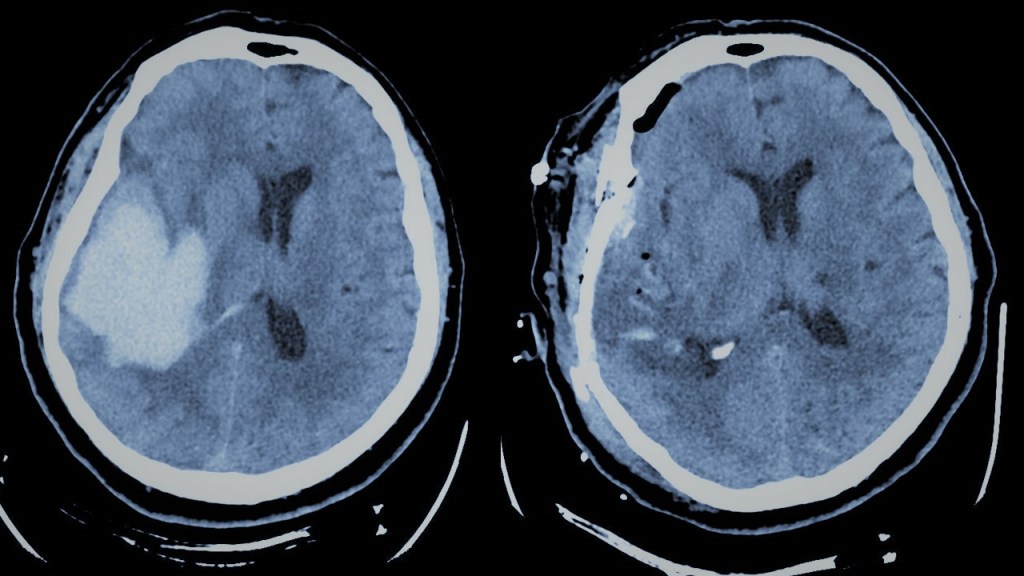

- Accidente cerebrovascular hemorrágico ó hemorragia cerebral espontánea: En él la hemorragia tiene lugar en el interior del parénquima cerebral. Su causa más frecuente es la hipertensión. En otros casos puede deberse al debilitamiento de los vasos sanguíneos debido a la “angiopatía amiloide”, típica de personas mayores de 70 años. Facilitada por los tratamientos anticoagulantes, puede también estar provocada por las lesiones previamente descritas (aneurismas, MAVs, tumores cerebrales, etc). Se trata de un cuadro grave que generalmente suele manifiestarse del mismo modo que un ictus. Ha de considerase la evacuación quirúrgica en caso de que la hemorragia alcance un volumen crítico, se acompañe de un deterioro del nivel de conciencia y se localice en un punto accesible.